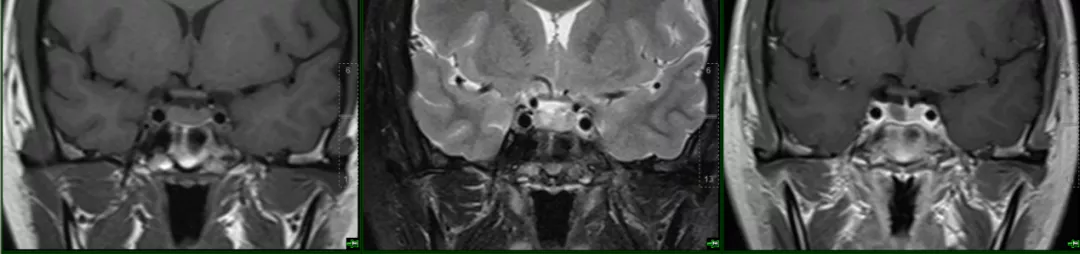

case 12:m/46y,无症状,偶发

垂体柄前方及中间部见两个 T1WI 等 T2WI 压脂低信号,增强无强化

case 13:

小条状 T1WI 高 T2WI 压脂略低增强无强化

case 14:女,39 Y

冠状位扁平,呈「蝴蝶结」状改变